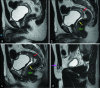

Disorder of sex development is an inclusive term that refers to any problem where the genital organ is atypical in relation to chromosomes or gonads. Ovotesticular disorder of sex development, which is formerly known as "true hermaphroditism," is the most rare form among all disorders of sex development in humans. It is characterized by the simultaneous presence of both ovarian and testicular tissues in the same individual and characteristically presents with ambiguous genitalia in neonates or infants. Herein, we present an unusual case of a 19-year-old individual with phenotypically nearly normal male genitalia who presented with the complaint of bilateral breast enlargement.